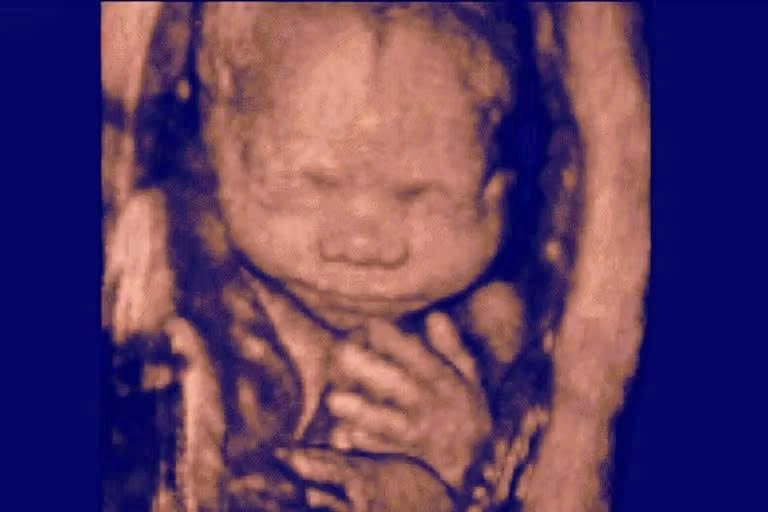

Acouple aborted a healthy preborn baby at six months after learning that the fertility clinic had given them someone else’s embryo.

An amniocentesis verified that the baby was not genetically related to the couple. According to the lawsuit, “Ms. Doe and Mr. Doe did not know what to do. They had grown to love this baby, who had already begun kicking. On the one hand, they did not want to lose her even if she was not genetically related to them. On the other hand, they could not imagine carrying a stranger’s baby to term, only to potentially lose her in later legal battles to her biological parents, which would be devastating to the entire family.”

On December 1, 2021, they aborted the baby they claimed to love because they feared the baby’s biological parents might want her.